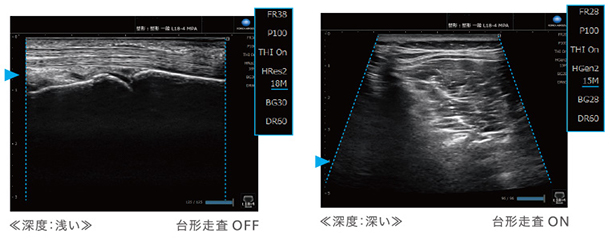

簡単操作で画像を最適化 MPA機能

表示深度を変更するだけで,あらかじめ設定した画質パラメータが適用されます。例えば,表示深度を浅くすると高周波に,深くすると低周波や台形へ自動的に切り替わります。